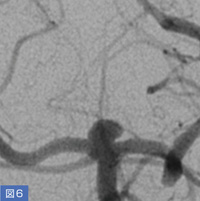

72歳、女性。未破裂脳底動脈先端部動脈瘤(図6)に対して瘤内塞栓術を行った。3D-DAで穿通枝の分岐部を確認し(図7)、塞栓術中も穿通枝の状態を確認しながら塞栓を進め、良好な塞栓を得ることができた(図8)。

図6 未破裂脳底動脈先端部動脈瘤(72歳、女性)

未破裂脳底動脈先端部動脈瘤(72歳、女性)